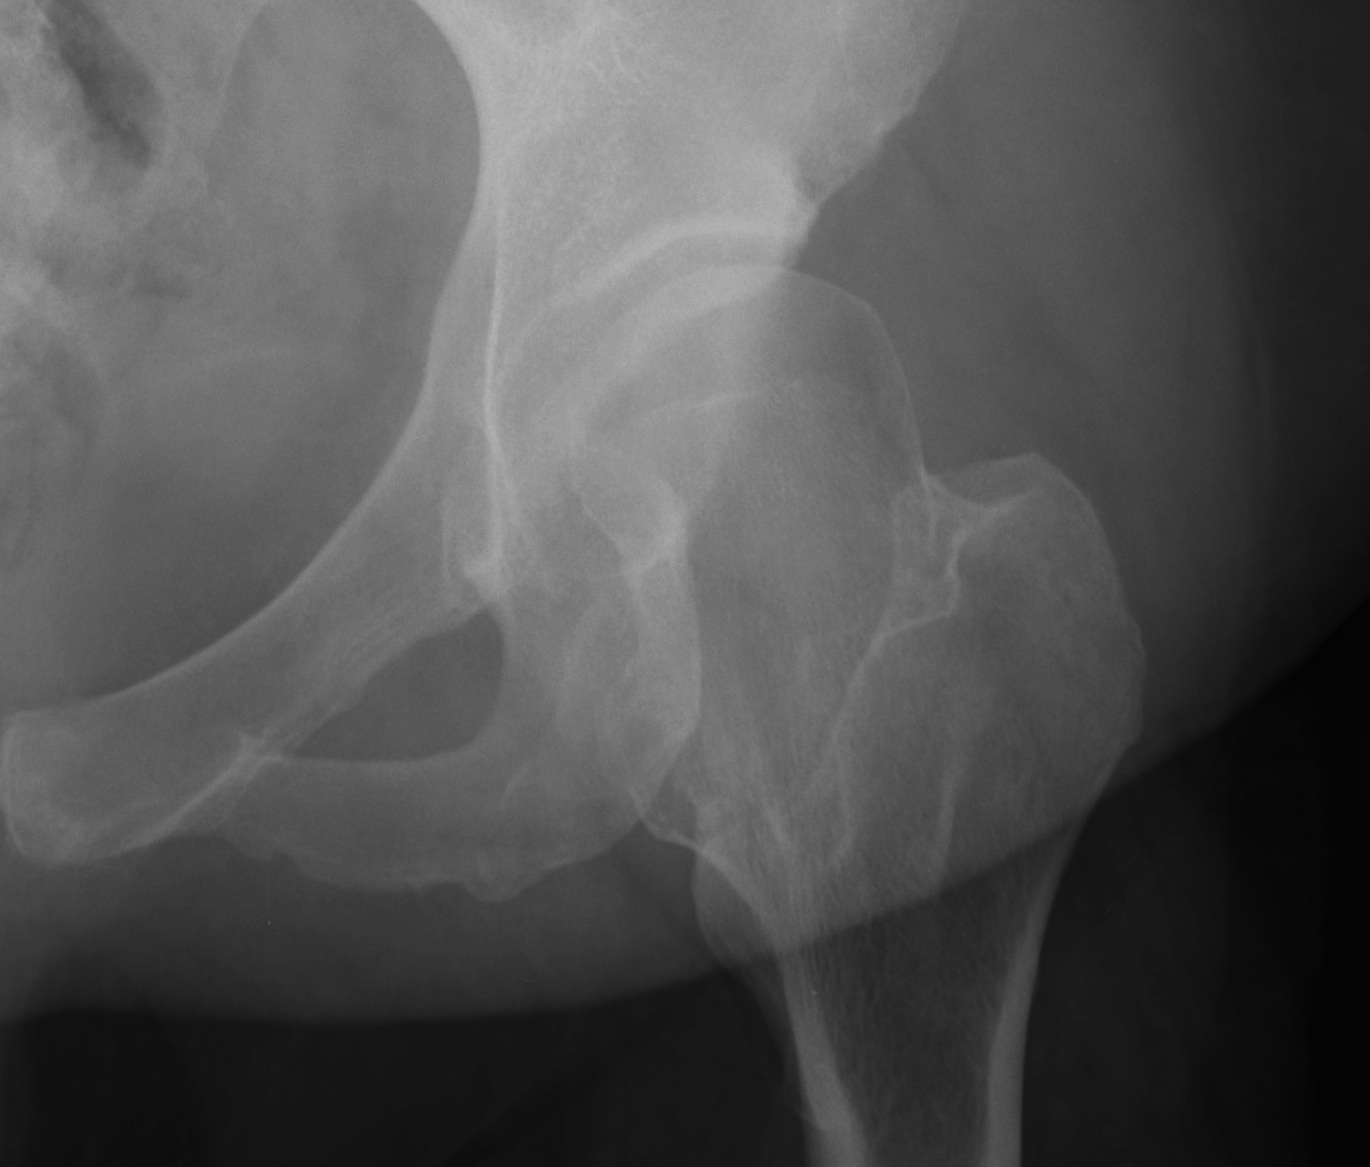

1. Salter

Concepts

- single osteotomy / innominate

- can do in older patient but difficult unless experienced with operation

- relies on motion at symphysis pubis to rotate acetabulum

Indications

- can't do bilateral Salters

- mild to moderate dysplasia / DDH

- concentric reduction

- near normal ROM

- no OA

- undeformed head

Advantage

- correct CE 10o

Disadvantage

- add 1 cm LL

- leave deficient posteriorly

Results

Salter CORR 1974

- 53 adults 4 year followup

- increased CEA by average 18°

- decreased AI average 50° to 38°

- 63% no pain / 40% no limp (compared with all patients preop)

- 79% trendelenburg negative (compared with 96% positive preop)